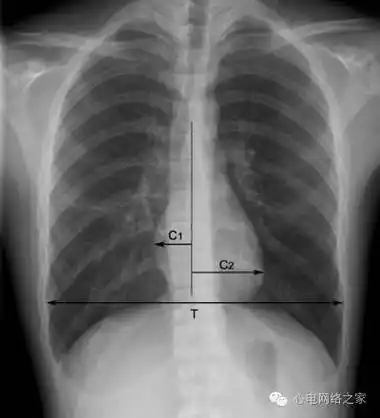

阅读x线胸片,这是一个靴形心脏的胸片.